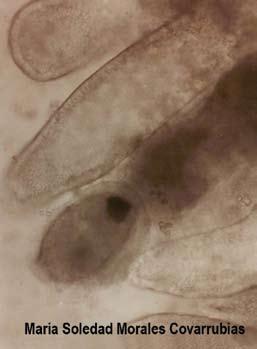

Figura 2. Corte histológico del epitelio del estómago donde se observan cuerpos de inclusión de WSSV en grado 4. Tinción de hematoxilina-eosina

El Virus de las manchas blancas (WSSV), presenta una prevalencia del 30 al 80% y mortalidades del 20 al 70%, principalmente en juveniles tempranos, donde se observan los cuerpos de inclusión en la mayoría de los órganos y tejidos (figura 2).